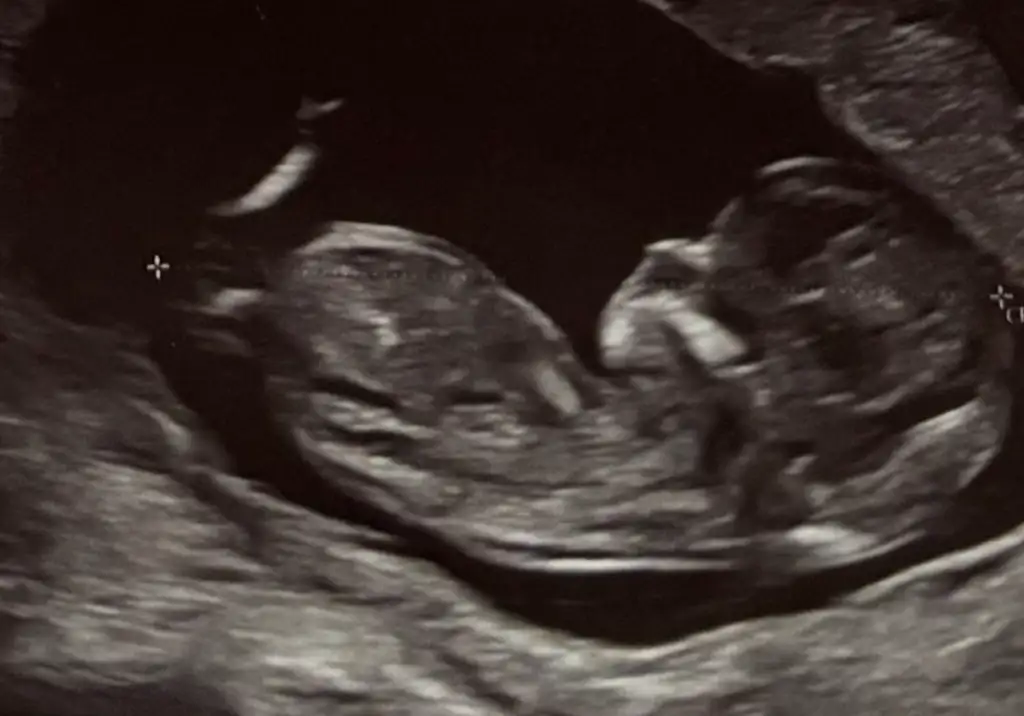

Kızlar bu ultrason görüntülerinden ben hiçbir şey anlayamıyorum, siz nasıl anlıyorsunuz ya 🙈 bunların açısı falan mı farklı olmalı anlayabilmek için, yoksa cinsiyet yorumu olan var mı? Chatgpt ye attım yorum yapmıyor, başka açıdan çekilmeli diyor. 12+0da çekildi bu görüntüler. Biz fetal dna yaptırdık ama yaptırdığımız yer yeditepe ünv hastanesi ve cinsiyet bilgisi paylaşmıyormuş. O yüzden oradan da öğrenemeyeceğim.

Ben kız diyorum çıkıntı olan yer daha yukarıda olsa erkek derdim bir de bacak arası gördüm sanki ve orası da boş :)